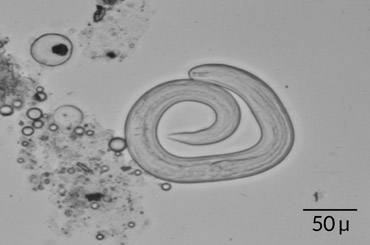

Lu and her colleagues confirmed the source of the infection by testing 20 centipedes they bought from the same market. The team discovered A. cantonensis larvae that could infect humans in seven of the centipedes. The infected worms had an average of 56 larvae each. The case is the first evidence that eating raw centipedes contaminated with worm larvae can transmit rat lungworm disease, the researchers report July 30 in the American Journal of Tropical Medicine and Hygiene.